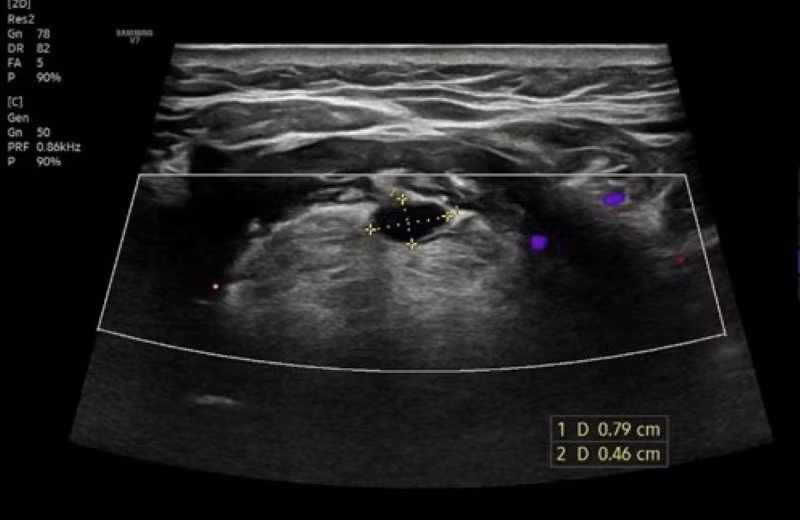

Hình ảnh siêu âm của bệnh nhân phát hiện bất thường.

Đáng chú ý, kết quả siêu âm tuyến giáp ghi nhận hình ảnh dạng nang ít cản âm - dấu hiệu quan trọng giúp loại trừ khả năng tuyến giáp lạc chỗ dạng đặc. Chính phát hiện này đã góp phần định hướng chẩn đoán chính xác, làm rõ tình trạng dị tật bẩm sinh hiếm gặp ở bệnh nhân. Chẩn đoán xác định, bệnh nhân mắc bệnh nang ống giáp lưỡi, được bác sĩ tư vấn hướng điều trị phù hợp.